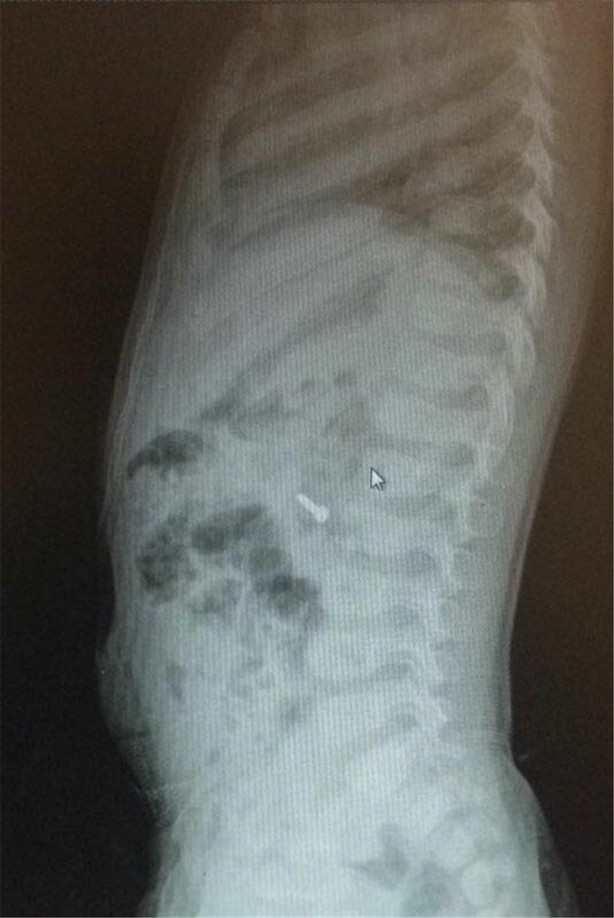

İzmir Tepecik Eğitim ve Araştırma Hastanesi Çocuk Gastroenteroloji Bölümü'nün, yabancı cisim yutan çocukların nefes ve borusu ile midelerinden çıkarttığı, anahtarlık, madeni para, saat pili, ataç, çengelli iğne ve çivi gibi objeler görenleri hayrete düşürdü.

Bu objelerden en tehlikelisinin piller olduğuna dikkat çeken Doç.Dr. Maşallah Baran, "Piller kimyasal mekanizmayla mukozayı yakıyor, özellikle yemek borusu çok duyarlı pillere, hele ki yeni takılmış bir pilse saatler içinde şahit olduğum bir kaç vaka var, yemek borusunu kömür haline getirebiliyor" dedi.